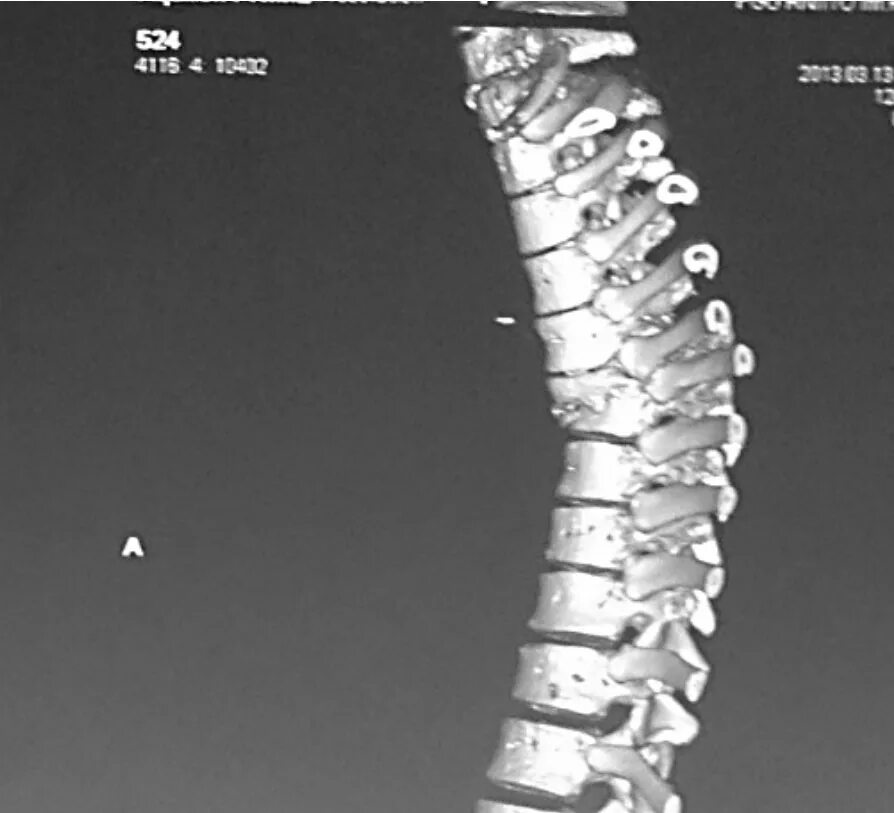

Перелом грудного позвонка код